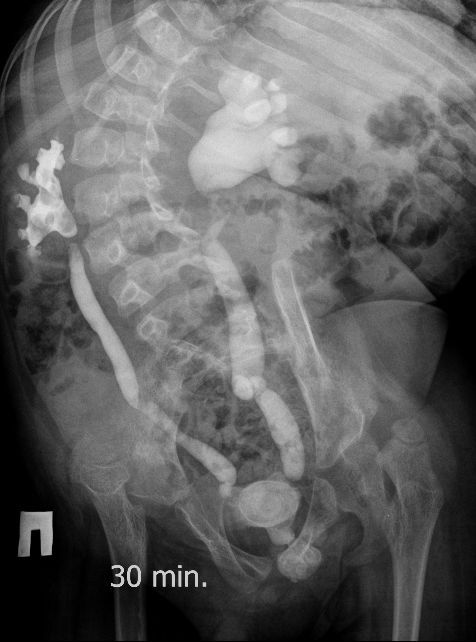

Поскольку откликов нет, добавляю экскреторные урограммы этого же пациента

Нейрогенный мочевой пузырь (?), МКБ, конкремент мочевого пузыря, двухсторонний мегауретер, конкремент правой почки.

И что законтрастировалось на экскреторных урограммах около мочевого пузыря?

Верификация:

Выдержка из протокола операции- "...вскрыт мочевой пузырь, обнаружен камень 4 х 3х 2.5 см, плотный, удалён. При дальнейшей ревизии мочевого пузыря обнаружен вколоченный камень в шейке мочевого пузыря и в уретре, удалён камень 2 х 1.5 х 1.5 см. При осмотре устья левого мочеточника - последний зияет, мочеточник расширен до 1 см, учитывая расширение мочеточника, проведена антирефлюксная пластика по Грегуару..."

На экскреторной урограмме - размеры собирательной системы левой почки уменьшились. Визуализирована расшиенная контрастированная проксимальная уретра.